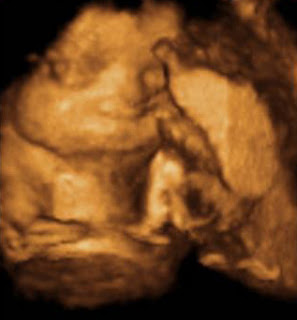

Welcome

Welcome to my Crib!

Come back often and check on status and my growth and to see pics and videos! I am still chillin in Mommy's tummy, nice and warm but I will be coming home soon! I can't wait to meet Mommy and Daddy! So stick around to see what happens next!!